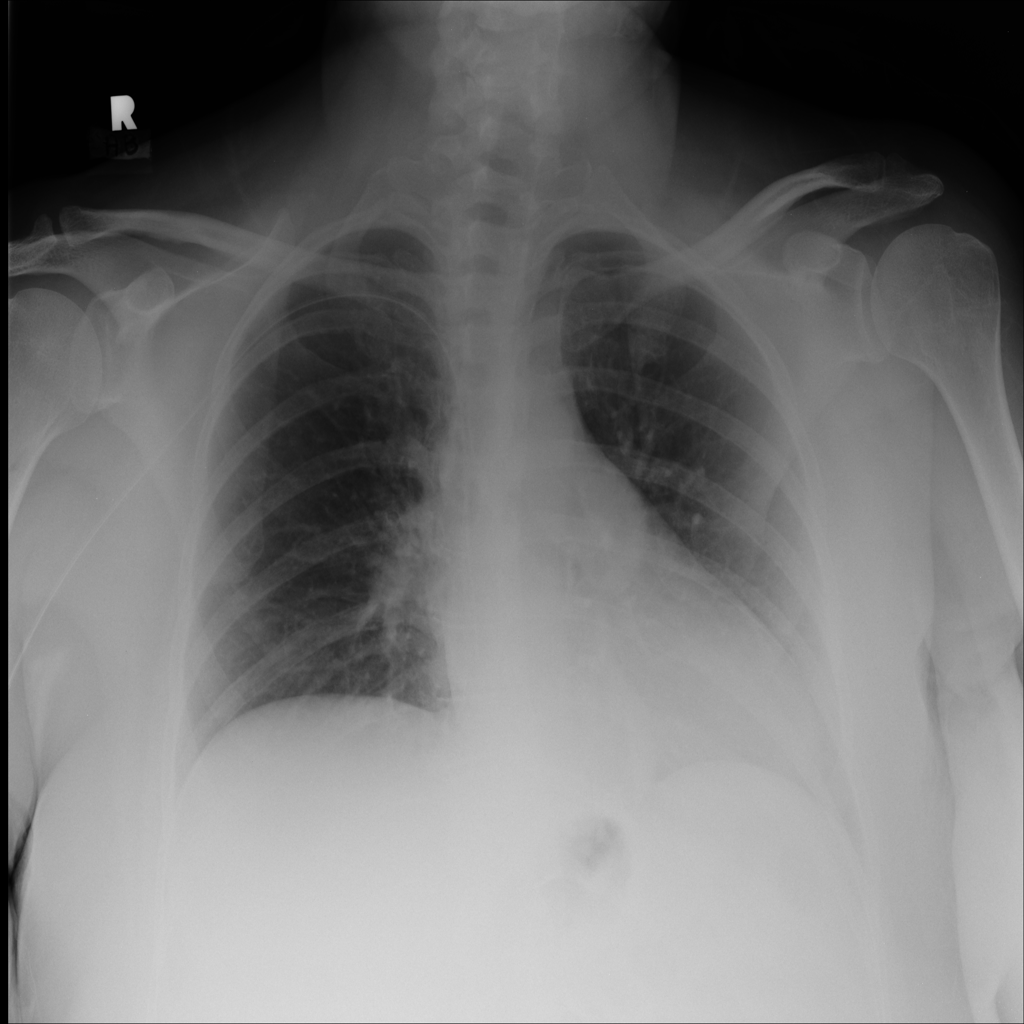

PAT-0ABD · IMG-000Hernia

PAT-0ABD · IMG-000

PA